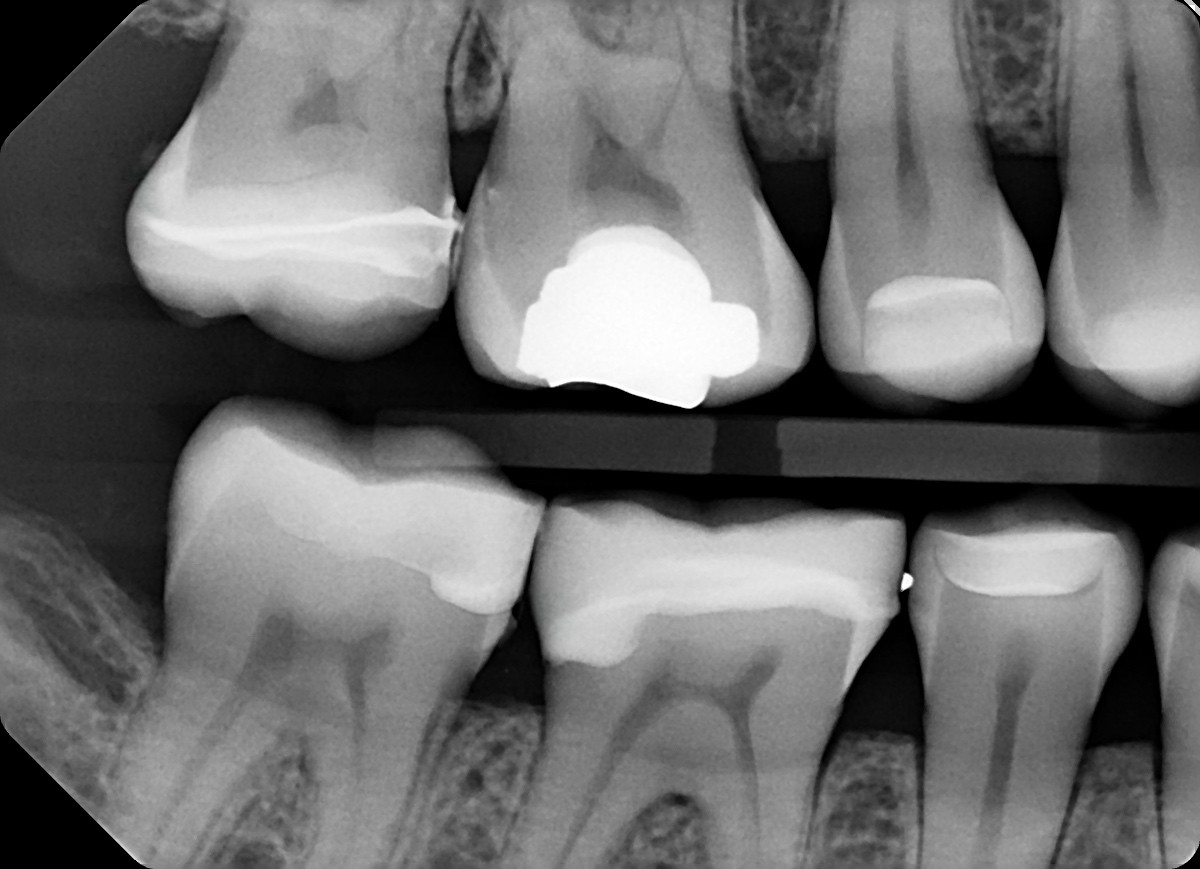

1. On which surface a recurrent caries can be detected?

2 / 35

2. On which surface a recurrent caries can be detected?

None of the teeth shows recurrent caries